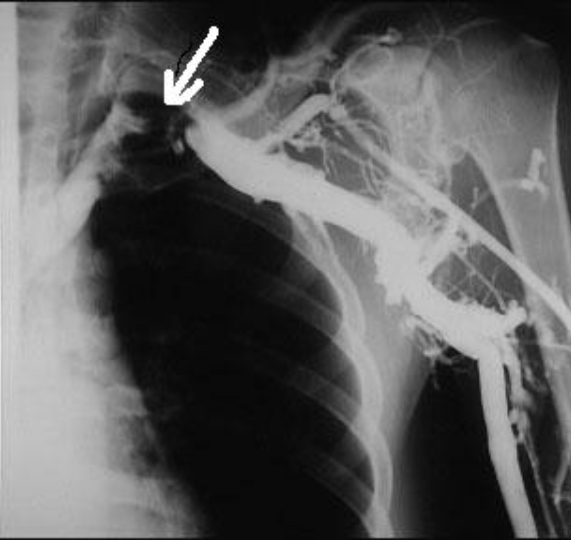

A 26-year-old left-handed healthy man presented with a three month history of repeated bilateral chest pain. Six months previously, he started heavy muscular activity of upper limbs (work out at a gym). Two months before he had been examined by his pulmonologist because chest X-ray revealed bilateral small effusion and tuberculin test had been positive. The patient started treatment as suspected tuberculous pleuritis and beside antituberculous drugs he used corticoids too. Despite treatment, difficulties remained and the patient was remitted to our clinic. On examination, there was no edema of the left arm, only prominent superficial veins on arm and left part of chest. On auscultation of the lungs, breath sounds were weakened bilaterally. Chest radiography revealed small pleural effusion. Electrocardiography and echocardiography were normal. Suspected pulmonary embolism was confirmed by computed tomography. DVT in lower limb was excluded by compression ultrasonography. Because the patient had prominent superficial veins on arm and left part of chest, we suspected left subclavian vein thrombosis, which was established by venography (Figure 1). Aortography revealed aneurysm of left subclavian artery (Figure 2) and also confirmed left thoracic outlet syndrome due to adherent first and second ribs (Figure 3), interruption of flow in left subclavian artery in abduction of left upper limb and appropriate flow in left subclavian artery in adduction of left upper limb (Figure 4). Patient was administered low molecular weight heparin as initial step, followed by the acenocoumarol therapy. A thrombophilia screen revealed prothrombin 20210A mutation, which was detected by polymerase chain reaction.

Figure 1: Venography of left upper extremity: Subclavian vein thrombosis marked by the arrow.